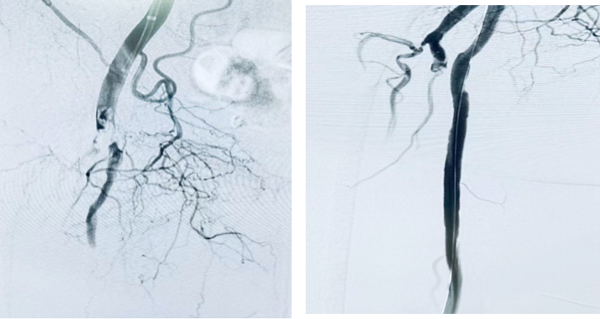

颈动脉狭窄采取腔内治疗的方式,通过股动脉穿刺置入血管鞘后,由股动脉置入造影导管,造影明确颈动脉狭窄情况,导丝选入颈动脉病变远端,沿导丝置入保护伞,沿保护伞导丝置入球囊预扩张病变,随后置入颈动脉支架,造影明确支架定位,准确释放颈动脉支架。造影见颈动脉狭窄消失,管腔恢复畅通。缝合穿刺点,患者术后24h可正常下地活动。

颈动脉狭窄术前;颈动脉狭窄治疗术后;颈动脉狭窄术前;颈动脉狭窄治疗术后